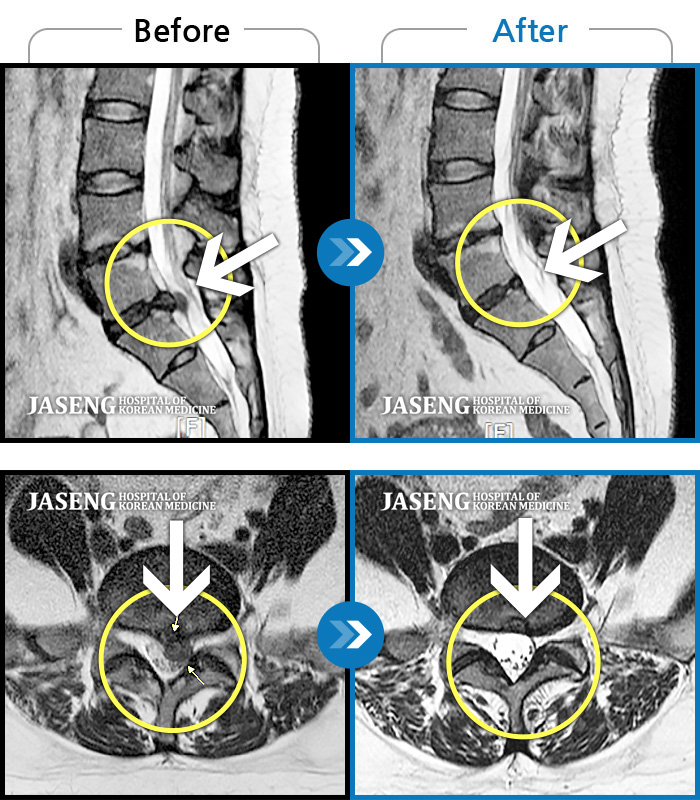

허리디스크

인천 · 조남훈 원장

허리가 너무 아프고 다리가 저려요.

촬영시기

2018.04.23 ~ 2025.12.05

2025.12.19